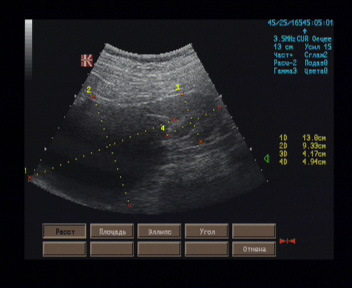

Правая почка - верхняя половина почки представлена жидкостной полость неправильной формы размерами 135 х 102 х 90 мм, имеющая гладкие стенки толщиной до 5 мм, однородное анэхогенное содержимое; нижняя половина почки размерами 73 х 48 мм, контуры неровные, паренхима толщиной 16 - 17 мм, однородная, равномерно гипоэхогенная, кортико-медуллярная дифференцировка не выражена, ЧЛС не расширена.

Эхографические признаки гигантской кисты правой почки, синусной кисты левой почки.